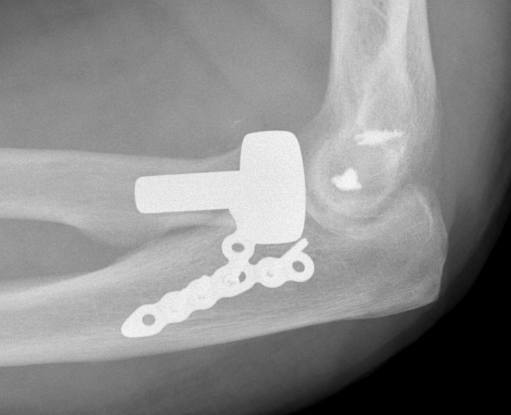

Medial approach and buttress plate with LCL repair

buttress plate

Universal posterior approach with radial head replacement and medial approach with medial buttress plate

Buttress plate - medial approach to anteromedial fragment

Medial buttress plate - large